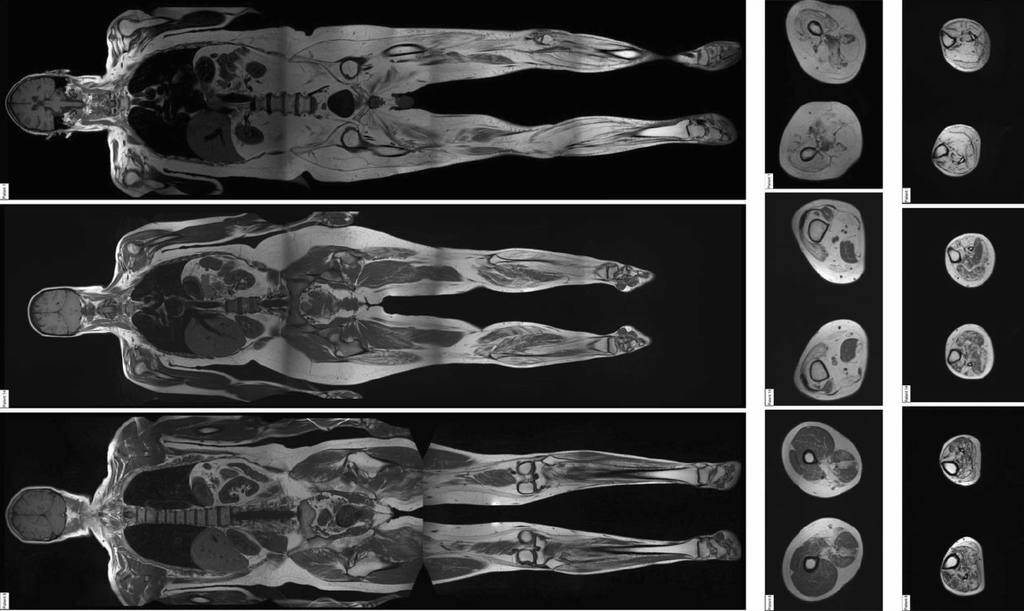

TotalView™ Whole-Body Scan

Our most comprehensive study, covering head-to-pelvis in one session. Ideal for broad preventive assessment or complex clinical questions that span multiple organ systems.